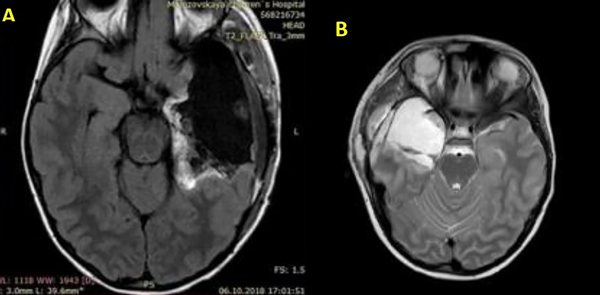

Figura 5. Dos ejemplos de amigdalohipocampectomía postoperatoria con lobectomías temporales anteriores. A corresponde a un lado izquierdo y B a un lado derecho, una de las técnicas de tratamiento quirúrgico de la Epilepsia Refractaria a los Medicamentos.

Figura 6. Ejemplos de escaneos de RM postoperatorios después de la extracción de tumores, los cuales fueron la causa de convulsiones epilépticas resistentes a los medicamentos. A: corresponde a una cavidad quirúrgica del giro temporal medio derecho y B: a una cavidad temporal posterior izquierda.